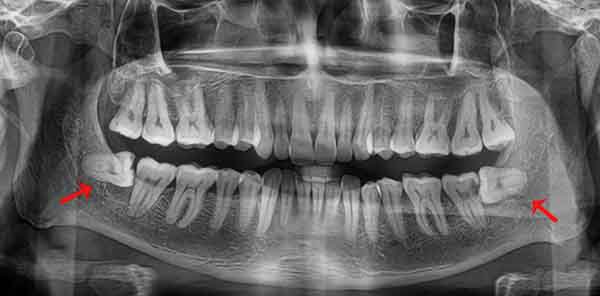

Chụp X-quang trước khi nhổ răng khôn